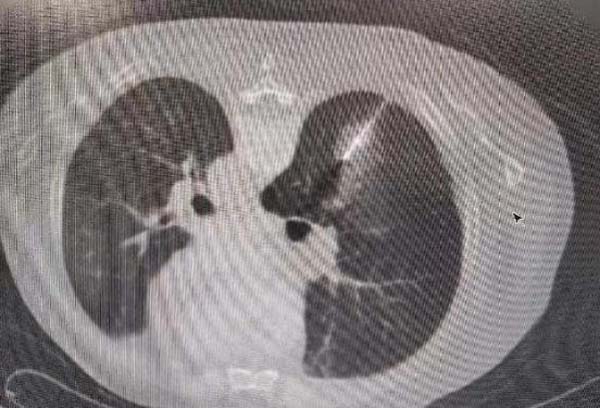

治疗后安全返回病房:

因此,本次手术方案中一次穿刺操作,既可以取得结节的病理结果,又可以消融结节,使患者在最小的创伤下得到最大的获益。